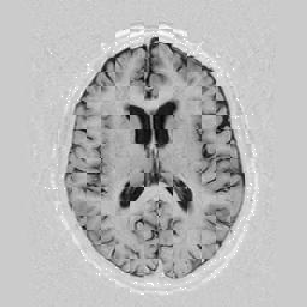

Lastly, Figure [*] shows 10 iterations at level 2, 6 iterations at level 1, and 6 at level 0.

Figure: Multi-scale NRR. From left to right, top then bottom: before NRR; after 10 iterations of NRR at level 2; after another 6 iterations of NRR at level 1; after 6 more iterations at level 0.